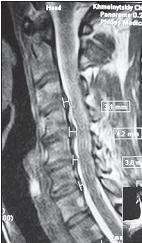

МРТ № 1

На магнитно-резонансной томографии (МРТ) № 1 — шейный отдел позвоночника, в относительно нормальном состоянии.

Шейный отдел позвоночника должен иметь нормально выраженный физиологический лордоз, не должно быть гиполордоза или гиперлордоза, а так же кифотических деформаций.

Ширина спинного мозга: сагиттально > 6–7 мм

1. Сагиттальный размер позвоночного канала на уровне:

СI 21 мм

СII 20 мм

СIII 17 мм

CIV-CVII = 14 мм

2. Высота межпозвонковых пространств:

СII < СIII < СIV < СV < СVII  СVII

3. Ширина спинномозгового канала: поперечный диаметр на уровне ножек: > 20–21 мм